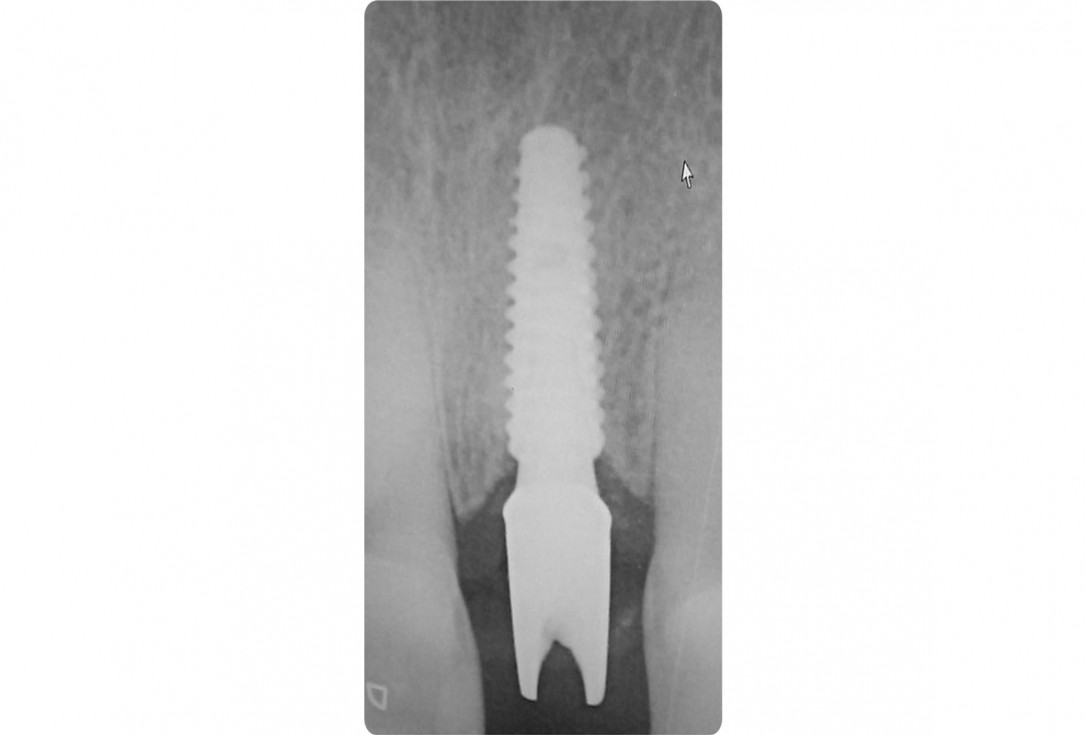

17/18 - X-ray shows good seating of dental implantTooth extraction and socket sealing with mucoderm® - Dr. A. Rossi